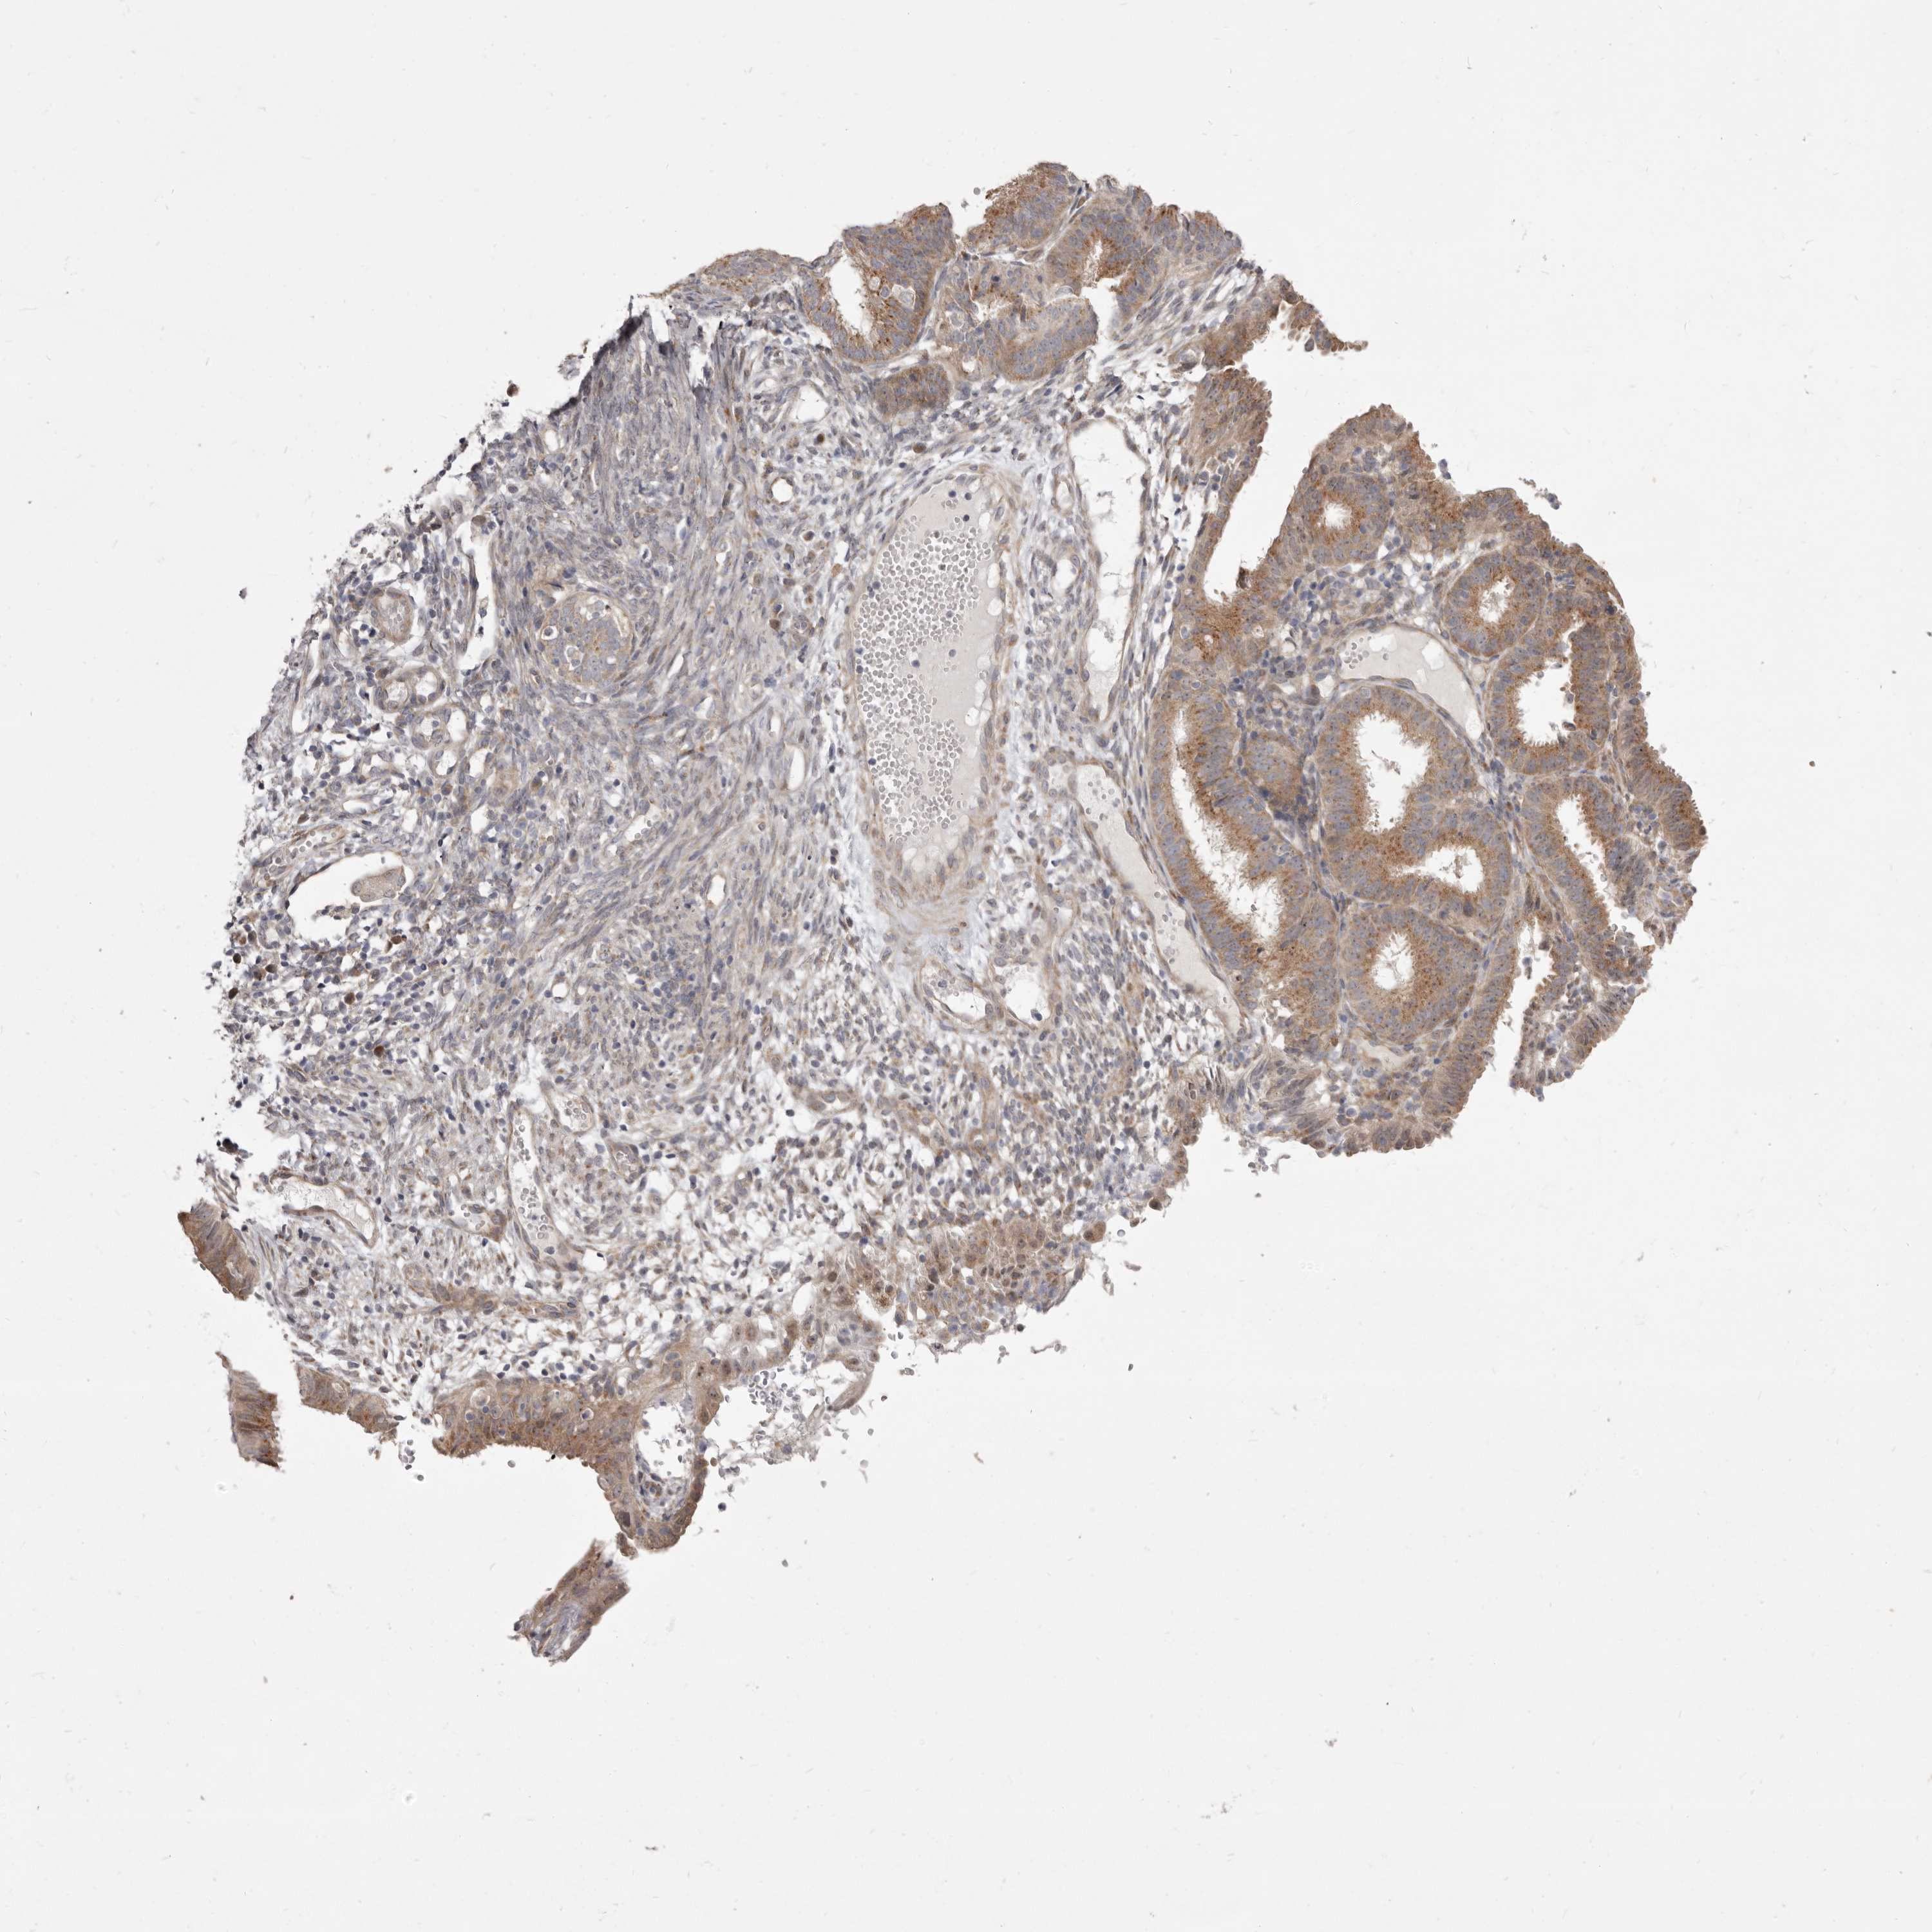

ENDOMETRIAL CANCER - Protein expressioni

A mouse-over function shows sample information and annotation data. Click on an image to view it in a full screen mode. Samples can be filtered based on level of antibody staining by selecting one or several of the following categories: high, medium, low and not detected. The assay and annotation is described here.

Note that samples used for immunohistochemistry by the Human Protein Atlas do not correspond to samples in the TCGA dataset.

Antibody stainingi

Antibody staining in the annotated cell types in the current human tissue is reported as not detected, low, medium, or high, based on conventional immunohistochemistry profiling in selected tissues. This score is based on the combination of the staining intensity and fraction of stained cells.

Each image is clickable and will lead to virtual microscopy that enables deeper exploration of all samples and also displays staining intensity scores, fraction scores and subcellular localization as well as patient and tissue information for each sample.

Antibody HPA023883

Antibody HPA027527

Staining

High

Medium

Low

Not detected

Intensity

Strong

Moderate

Weak

Negative

Quantity

>75%

75%-25%

<25%

None

Location

Nuclear

Cytoplasmic/membranous

Cytoplasmic/membranous,nuclear

Adenocarcinoma, NOS

Adenoma, NOS

Adenocarcinoma, metastatic, NOS